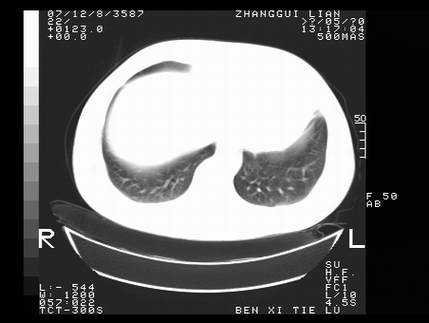

标题: CT10817:女,46,胸疼,无其他病史 [打印本页]

标题: CT10817:女,46,胸疼,无其他病史

1 左侧中央型肺癌伴阻塞性肺炎 2 左肺门及纵隔淋巴结转移!3两侧胸腔及心包积液.

左肺中央型肺癌伴左肺上叶阻塞性肺炎两侧胸腔积液纵隔窗不清楚

支持考虑左肺中心性肺癌并左肺门及纵隔淋巴结转移,左肺阻塞性肺炎,心包积液.

左侧胸廓塌陷,纵隔向左侧移位,左上肺不张。

1 左侧中央型肺癌伴阻塞性肺炎

2 左肺门及纵隔淋巴结转移!

3两侧胸腔及心包积液.